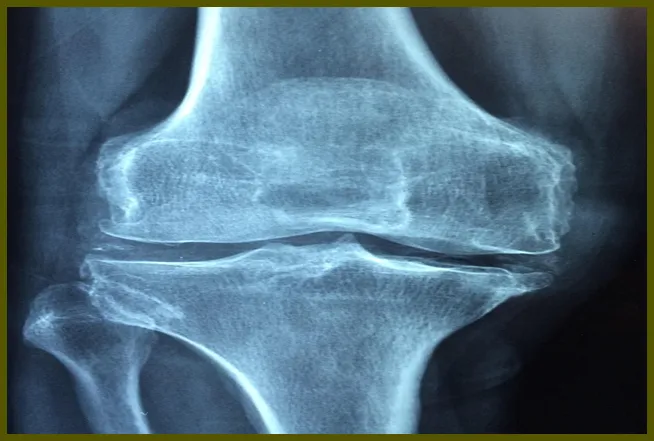

류마티스 관절염을 진단하는 과정

정확한 진단을 위해서는 전문적인 의료진과의 상담이 필요합니다. 다수의 증상들이 류마티스 관절염과 유사한 경우가 있어, 다음의 방법들이 진단에 활용됩니다:

- 신체 검진: 관절의 통증과 부종을 확인합니다.

- 실험실 검사: 혈액 검사를 통해 염증 수치를 확인합니다.

- 영상 검사: X-ray나 MRI를 통해 관절의 상태를 파악합니다.

이러한 절차를 통해 정확한 진단을 받을 수 있습니다.